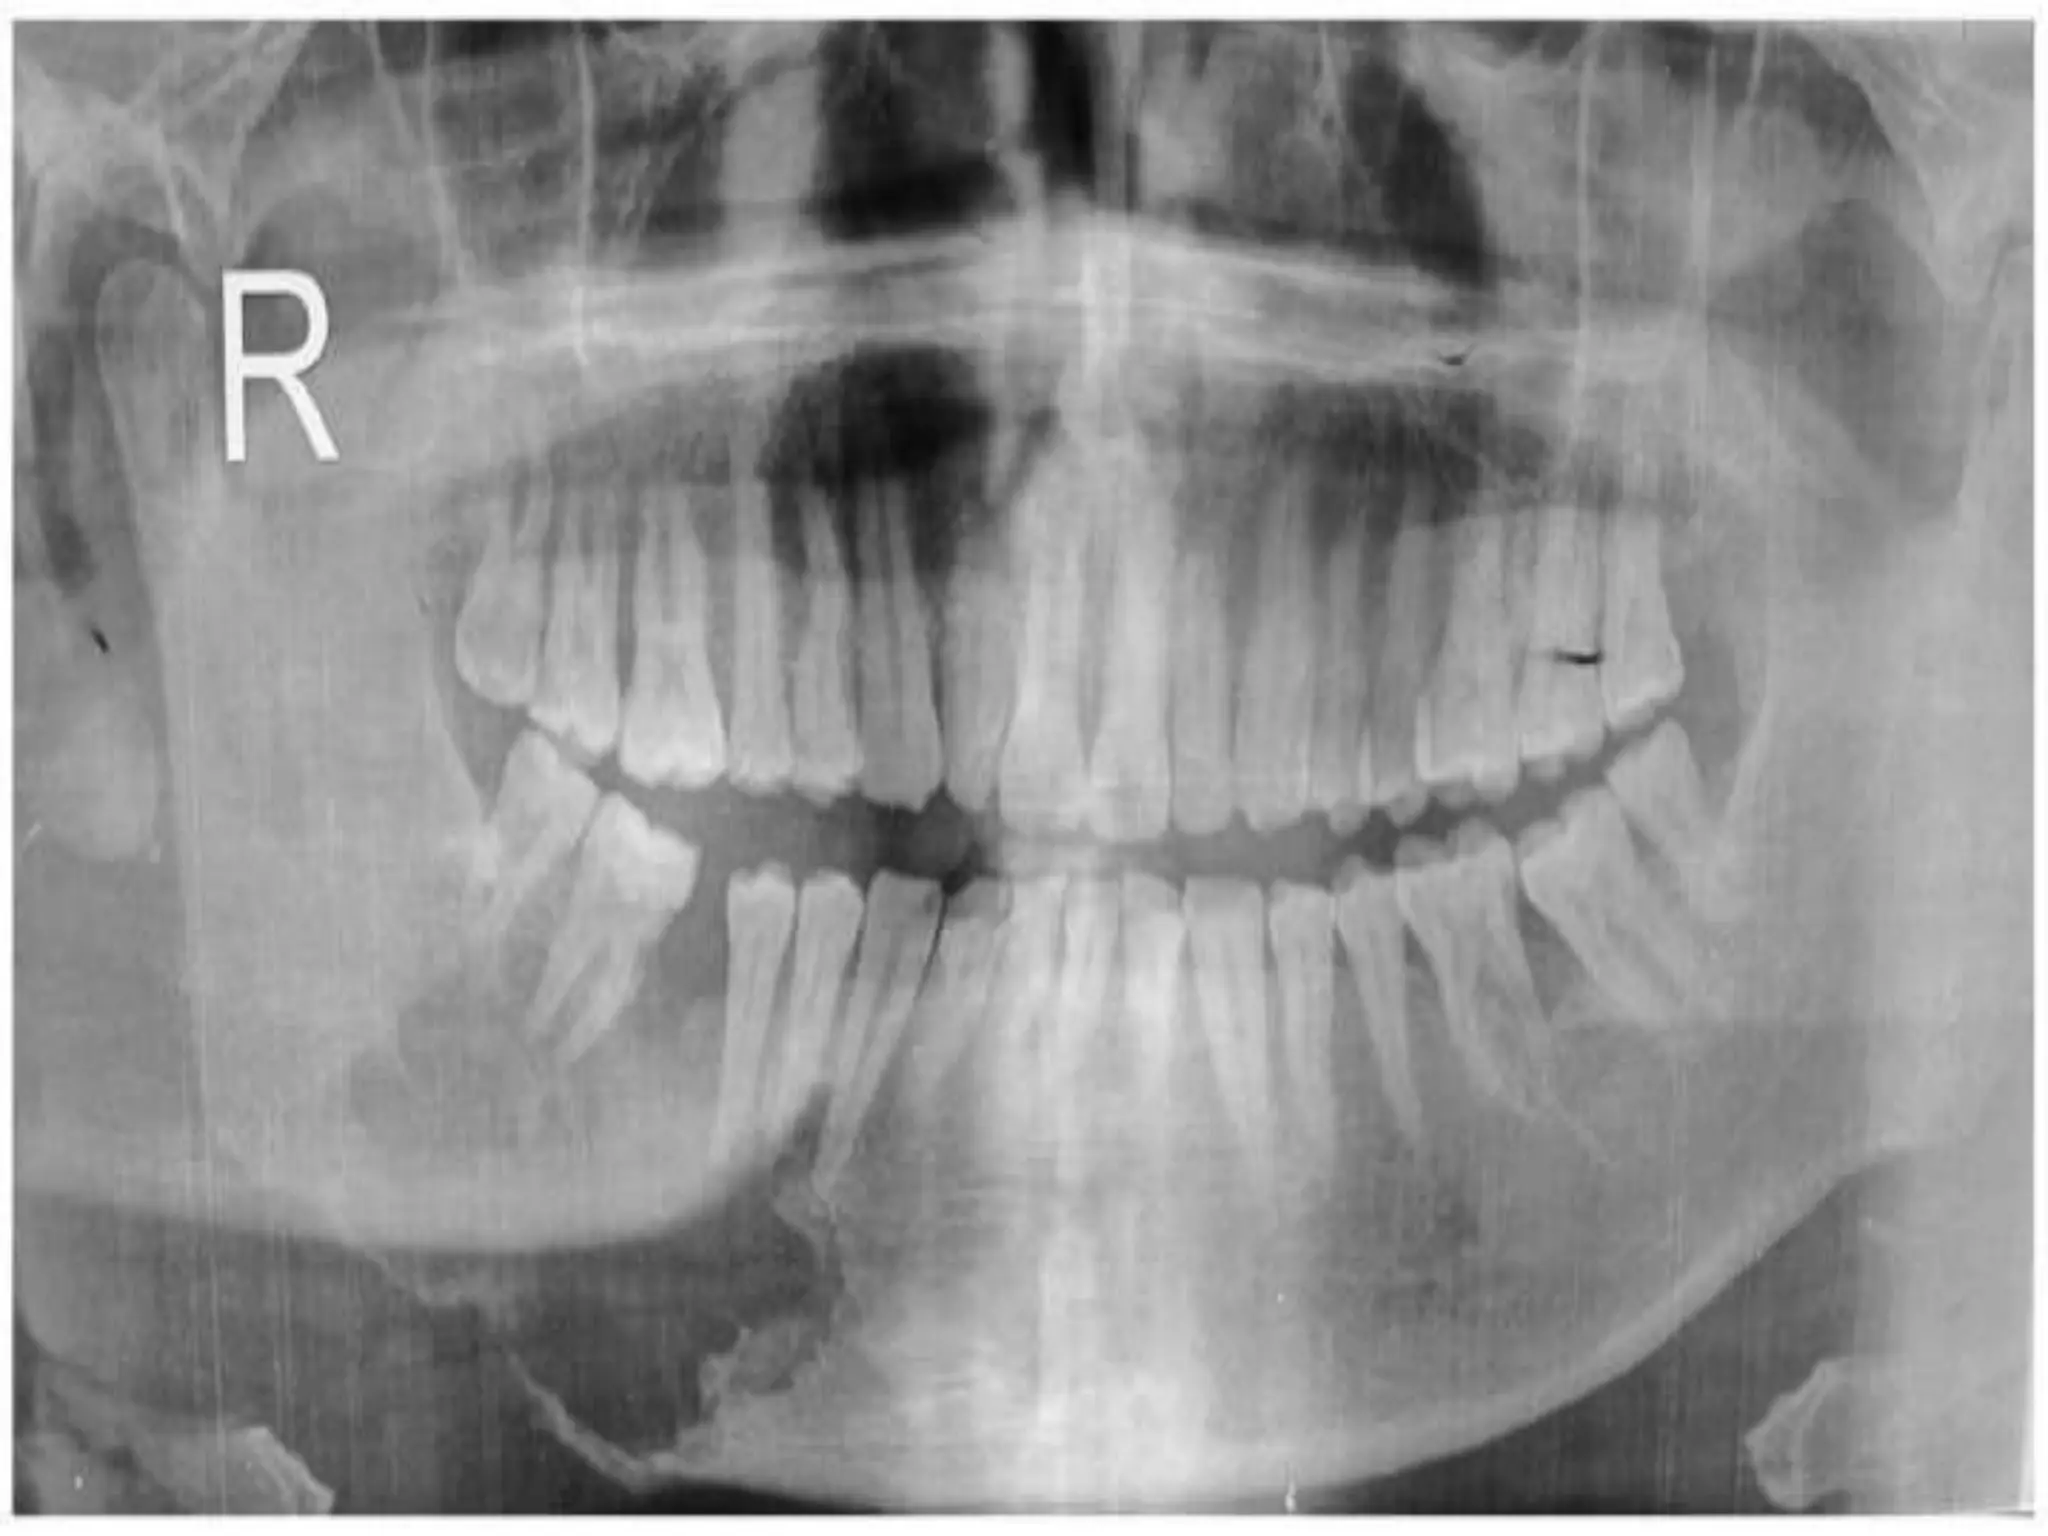

• #23 Orthopantomogram showing expansile lytic lesion in the body of mandible involving the roots of premolars, first and second molars. The lateral aspect of the lesion shows faint radiopacity

• #24 JUVENILE Occlusal radiograph marked with arrows showing buccal palatal extension of lesion with ossifications Intraoral periapical radiograph showing mixed radiodensity marked with an arrow, 14, 15 teeth show root divergence